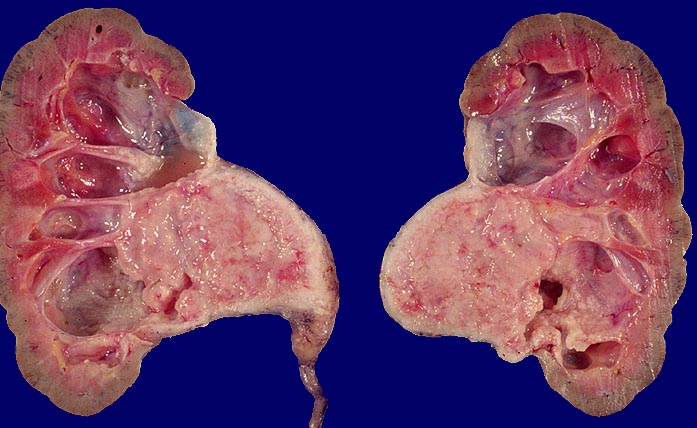

Pathomorphologisch unterscheiden sich Urothelkarzinome bei Phenacetinabusus nicht von sporadischen Urothelkarzinomen abgesehen von ihrer bevorzugten Lokalisation im Nierenbecken und der allenfalls ausserhalb des Tumors in der Harnwegsschleimhaut nachweisbaren Kapillarosklerose.

Der Abusus Phenacetin, bzw. Paracetamol- haltiger Mischanalgetika führt zu einer Vermehrung von Harnwegstumoren um einen Faktor 10. Die Häufung ist noch markanter für Nierenbeckentumoren und beträgt für diese Lokalisation das 50 fache verglichen mit Nicht-Abusern. Normalerweise machen Karzinome des Nierenbeckens etwa vier bis neun Prozent aller Nierenkarzinome aus. In Gegenden mit gehäuftem Auftreten von Analgetikanephropathie steigt diese Zahl auf bis zu 30 Prozent. Harnblasentumoren sind sechsmal häufiger. Analgetikaabusus ist definiert als nicht bestimmungsgerechte tägliche Einnahme von Phenacetin- bzw. Paracetamol- haltigen Mischanalgetika länger als ein Jahr. Das Risiko für die Entwicklung (terminaler) Nierenschäden steigt ab einer kumulativen Dosis von 0.5 bis 1 kg Paracetamol in Mischanalgetika.

Morphologische Merkmale:

• Solider Tumor mit fokalen Entzündungsinfiltraten.